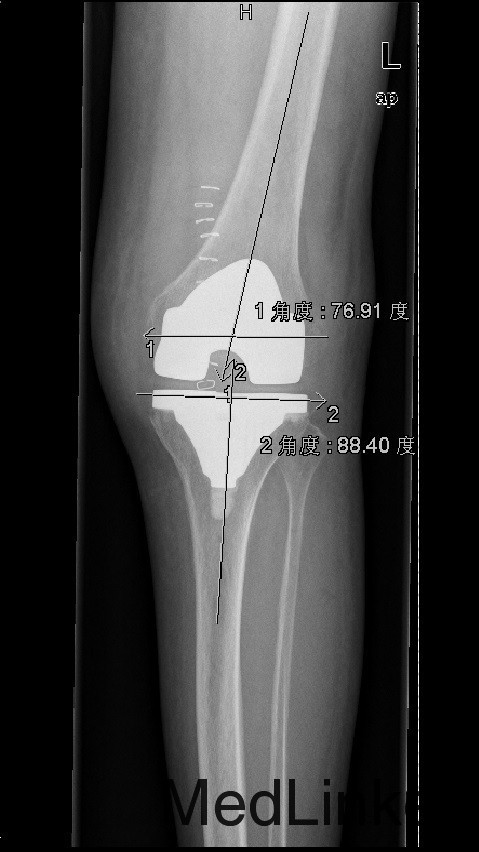

诊断:1、左膝骨关节炎伴屈曲畸形 2、左髌骨骨折骨愈合 治疗:积极行术前准备后于全麻下行左侧全膝关节置换术+软组织松解术,术后常规治疗。

患者术后功能良好,症状缓解,生活治疗提高 1、股骨外翻截骨如何在X线片上定角度?